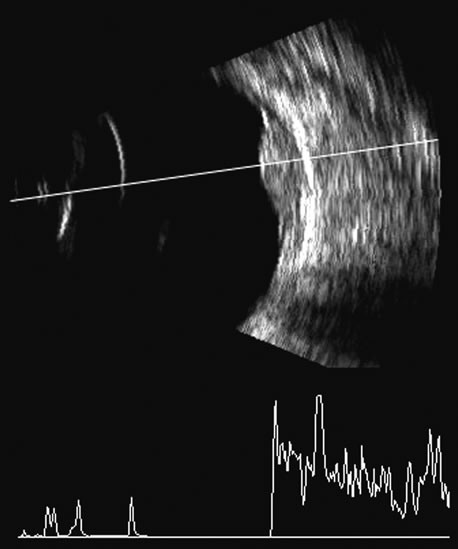

Malignant melanoma varies in its ultrasound presentation from a relatively homogeneous to heterogenous lesion on B-scan. The typical uveal melanoma absorbs sound so that the posterior section is relatively less echoic than the anterior aspect, producing a gradually decreasing amplitude, often to baseline on the A-scan (Fig. 21).

Fig. 21. An ocular tumor at the posterior pole showing the smooth convex border and solid internal reflectants typical of a melanoma.

Melanomas also have varying amounts of melanin, a highly acoustically reflective pigment. As noted, melanomas characteristically show high reflectivity anteriorly, with decreasing reflectance as the sound traverses the tissue. This produces the decreasing amplitude posteriorly in the tumor seen on A-scan and gray-scale B-scan. This effect often enhances the anterior scleral boundary. The posterior tumor border is thus measured as the first “rising” echo from the tumor decline, and it is most easily seen and accurately identified on B-scan.27

Spectral parameter imaging, a digital signal processing technique that examines the frequency content of backscattered ultrasound signals, has been shown to be predictive of increased lethality in certain patients and also to be useful in the in-vivo identification of high-risk melanomas for treatment staging.46–48 The shape, density, orientation, and number of scattering elements in a region influence not only the relative amplitude or brightness of a pixel on B-scan but the frequency content of the signal returned to the transducer.19 The concept of differentiating tissue backscatter in a quantitative manner rather than in simple qualitative descriptions of hypo-, iso-, and hyperechoic variations in gray scale allows for maximum use of information available in the digital ultrasonograms. These techniques can be extended to examining the functional anatomy of the eye as well as disease states other than solid tumors (Fig. 26).

Fig. 26. A gray-scale B-scan of a large collar-button melanoma (top) showing a relatively isoechoic button and base with some differences in internal speckle noted. The companion serial plane spectral parameter image (bottom) shows local differences in the size of ultrasound scatterers within the tumor, with size range increasing from blue to red.